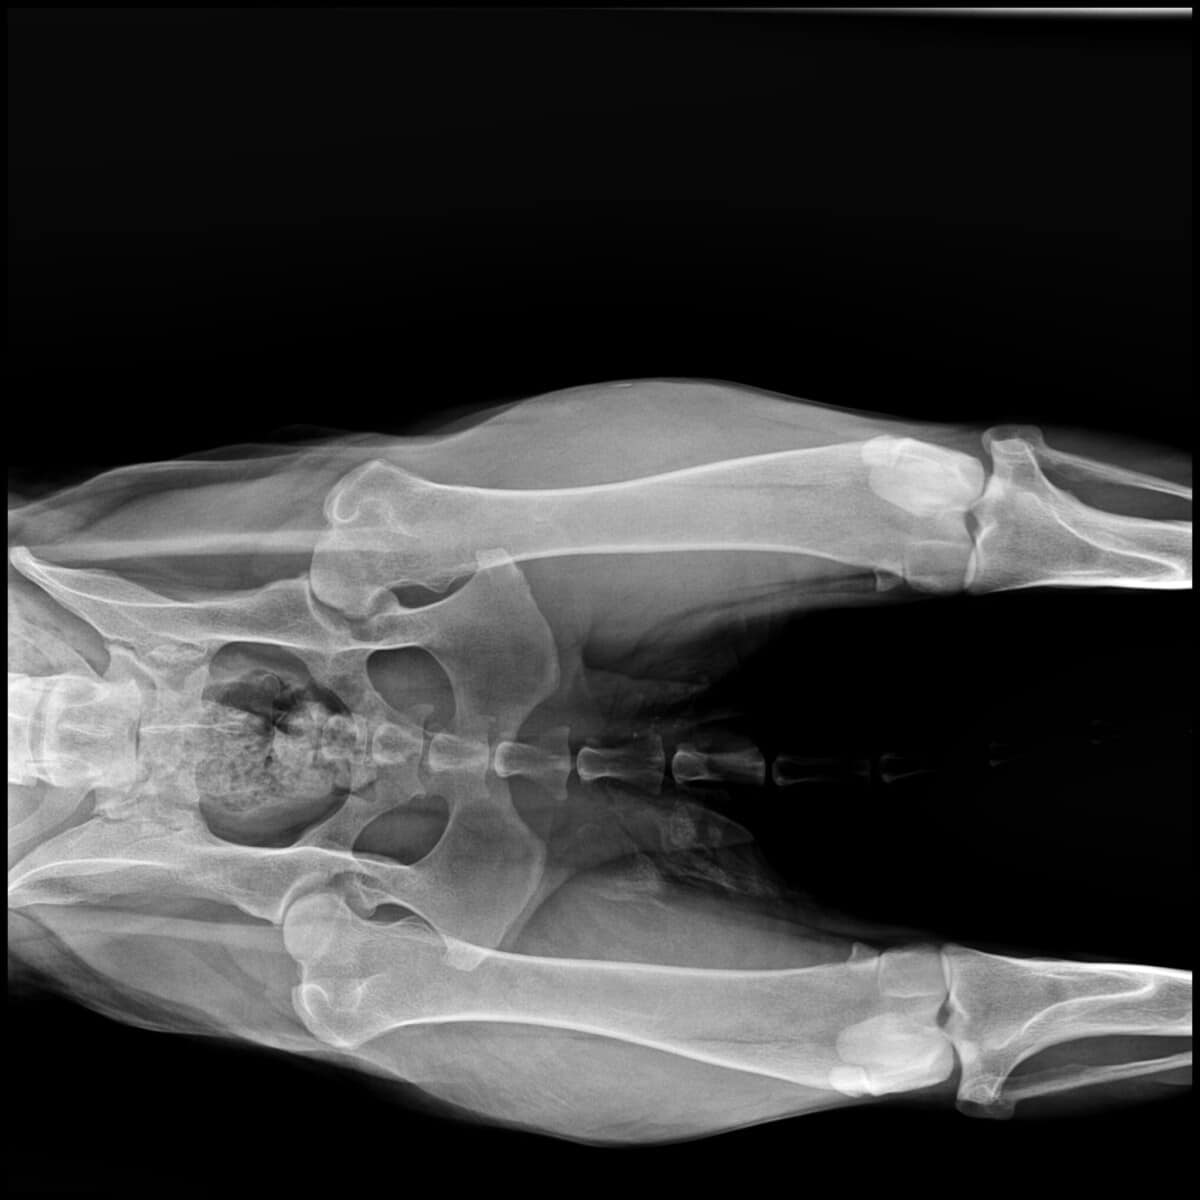

Olen iloinen, aktiivinen ja rakastan kaikkia ihmisiä! Mutta tarhalla huomasivat, että kävelen takajaloillani oudosti. Kun minut vietiin tutkittavaksi, eläinlääkäri antoi ikävän uutisen: minulla on vaikea-asteinen lonkkadysplasia molemmissa lonkissani.